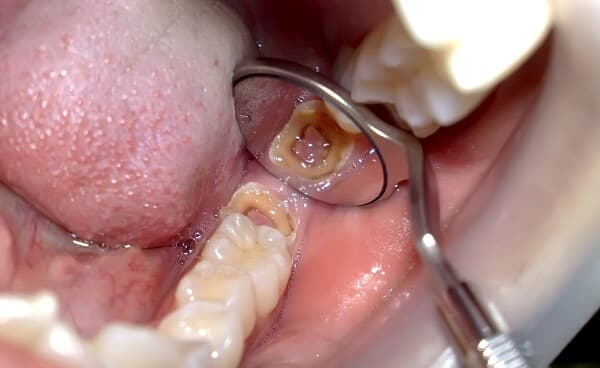

Hình ảnh răng hàm đã bị sâu nặng cần điều trị tủy ngay.